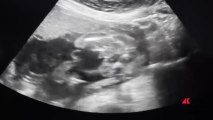

Fecondazione assistita eterologa. In attesa delle linee guida da parte del Ministero della Salute, sono stati resi noti alcuni punti che ora sono oggetto di discussione. Anche il centro di Fisiopatologia della Riproduzione di Cattolica si sta preparando ad incontrare le prime coppie che, in seguito, si sottoporranno alle terapie.<br /><br />Nel video intervista al Dott. Carlo Bulletti, primario del reparto PMA (Procreazione Medicalmente Assistita) dell'Ospedale Cervesi di Cattolica, che interviene sulle probabili linee guida.